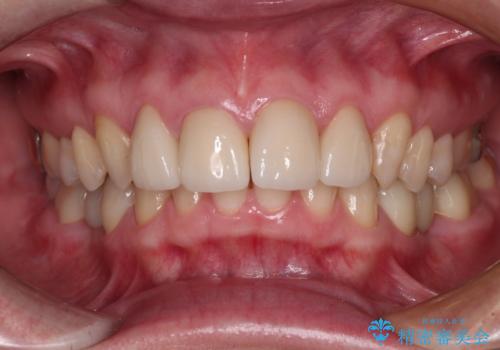

[ セラミック・インプラント全顎治療 ] 長年悩まされている歯の治療にケリをつけたい

![[ セラミック・インプラント全顎治療 ] 長年悩まされている歯の治療にケリをつけたいの症例 治療後](https://seimitsushinbi.jp/wp/wp-content/uploads/2022/01/f4f9ee9ff7018c558de74748d97a4667-500x350.jpg?v=1642042445)